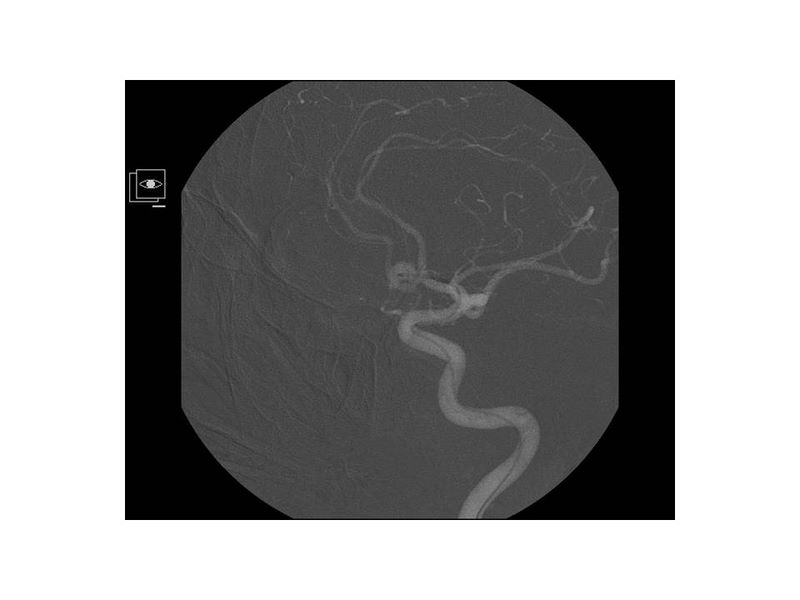

Aneurismas